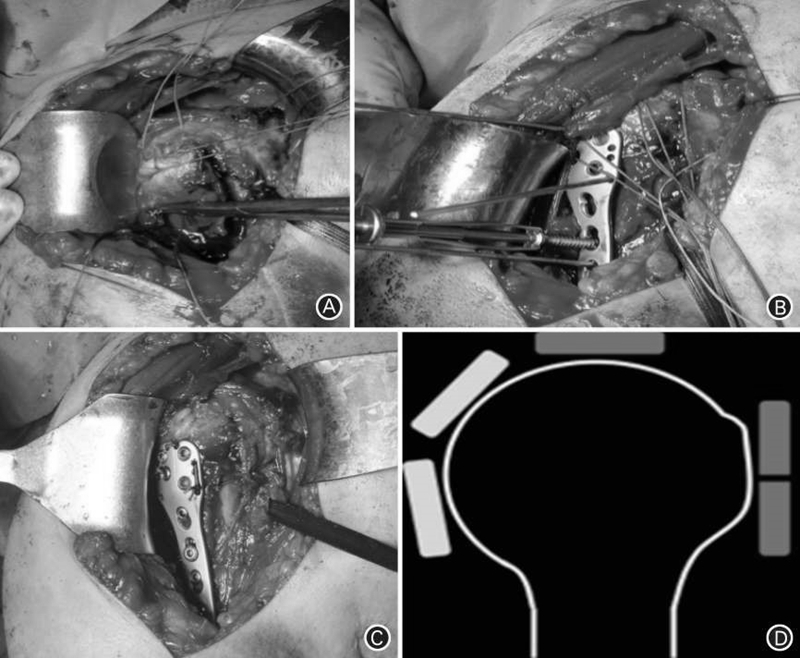

手术体位可以选择仰卧位或沙滩椅位,手术床应能透过射线,术中借助影像增强器透视了解骨折复位的情况和检查内固定钢板的位置及螺钉深度。常用的手术入路为三角胸大肌入路和经三角肌入路,这两个手术入路对肱骨近端骨折的复位质量和临床疗效类似,但是后者的手术时间较短。应重视大小结节骨折解剖复位和固定,以利于术后肩袖功能的恢复。肱骨近端解剖锁定钢板结合规范的缝线固定后,能有效维持结节骨折块复位(图1)。考虑到骨质疏松性骨折的特点,肱骨远端螺钉宜采取双皮质固定方法。

图1 肱骨近端解剖锁定钢板结合规范的缝线固定。 A. 高强度缝线分别穿过肩袖肌腱和大、小结节交界处;B. 牵拉缝线复位结节骨折块,缝线固定至锁定钢板的缝线孔;C. 肱骨近端解剖锁定钢板结合缝线固定粉碎性肱骨近端骨折;D. 借助“软组织合页” 作用,大小结节的解剖复位和固定有助于肱骨头间接复位:冈上肌和肱二头肌长头限制肱骨头向上方移位,冈下肌和小圆肌限制肱骨头向后方移位,肩胛下肌限制肱骨头向前方移位